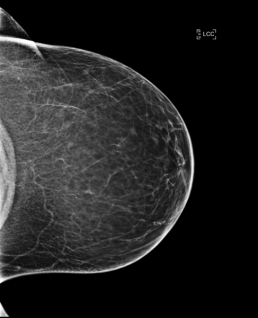

During the mammography reading, the radiologist finds a suspicious asymmetry and possible distortion on the right breast in CC, both on 2D and on tomosynthesis, without finding a match in MLO.